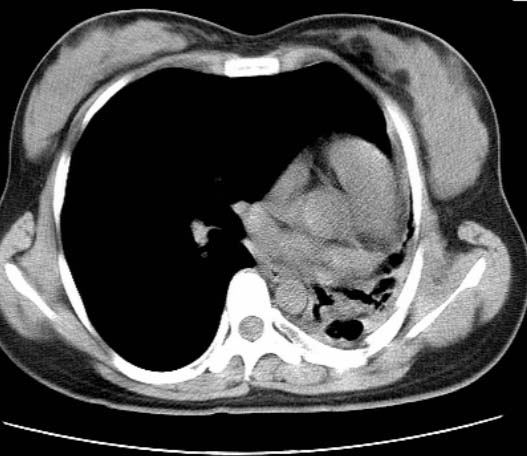

女  20岁。一月前咳血,诊“肺结核”抗痨治疗一月后,咳血停止,现复查。病人精神好。前后ct片对比未见明显变化。既往体检“正常”

1)考虑左肺结核并肺不张、支气管扩张。2)纵隔疝。

考虑左肺结核,左肺毁损,纵膈左偏,既往体检正常不可靠,tb一个月也不会这个样子的,有钙化,应该病程较长,冰冻三尺非一日之寒!

左肺发育不全。

考虑左肺结核,左肺毁损,纵膈左偏,既往体检正常不可靠,tb一个月也不会这个样子的,有钙化,应该病程较长,冰冻三尺非一日之寒

结核,左肺毁损。